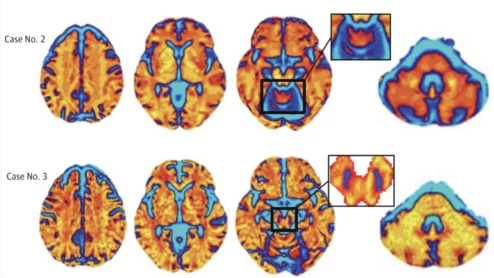

American Society of Echocardiography (ASE) President David H. Wiener, MD, FACC, FAHA, FASE, director of clinical operations at the Jefferson Heart Institute, and a clinical professor of medicine at Thomas Jefferson University, explains the growing number of multimodality cardiac imaging experts and how imaging societies need to change to meet their needs.

ASE President David Wiener detailed some of the many ways imaging societies need to adapt now that so many imagers are specializing in multiple modalities. It may be time to change how annual conferences are scheduled, for example, so that the costs of travel are easier to manage.